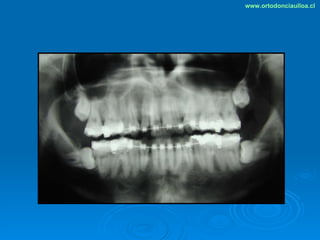

Este documento presenta dos casos clínicos de pacientes que recibieron tratamiento de ortodoncia. El primer caso fue de una paciente femenina de 14 años con apiñamiento dental y mordida cruzada que fue tratada mediante extracción de premolares y alineamiento dental. El segundo caso fue de un paciente masculino de 14 años con clase II esqueletal y desarmonía dentomaxilar que fue tratado con extracción de premolares y corrección de mordida. Ambos casos mostraron mejoría después de 3 años de tratamiento.